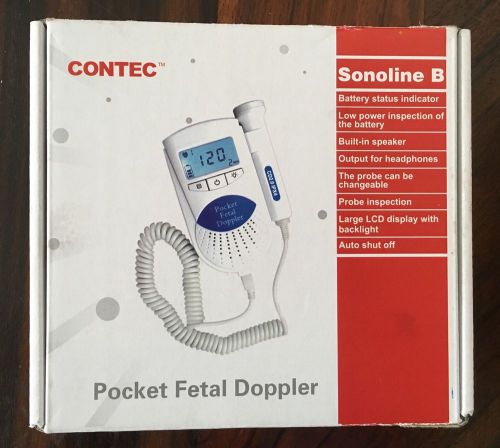

Sonoline B Pocket Fetal Doppler Pink

Contec Fetal Doppler Baby Heart Beat Monitor Ultrasound Doppler Sonoline B